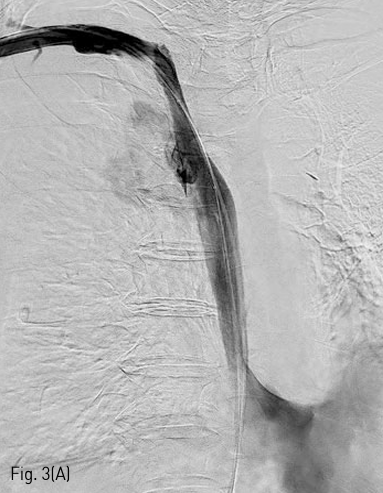

국소 마취를 시행하고 우측 대퇴정맥을 천자하여 0.035 인치 유도 철사 (Terumo, Tokyo, Japan) 와 5F C2 catheter (Cook, Bloomington, IN) 를 이용하여 catheter를 우측 쇄골하정맥에 위치시키고 시행한 정맥조영술에서 상대정맥의 협착을 확인하였다 (Fig. 1). 0.035 인치 유도철사를 따라 직경 10mm, 길이 4cm sized balloon catheter (ATB advance; Cook, Bloomington, IN) 를 삽입하여 상대정맥의 협착부위에 대해 풍선 확장술을 시행하였다 (Fig. 2). 10mm balloon으로 확장 중 waist가 발생하였으며 6 atm 시 waist가 소실되었다 (nominal pressure 5 atm, burst pressure 14 atm). 풍선 확장술 시행 후 시행한 정맥조영술에서 상대정맥에 조영제 유출과 우측 폐에 혈흉이 관찰되었다 (Fig. 3A, B). 이에 즉시 0.035 인치 유도철사를 따라 직경 10mm balloon catheter를 다시 삽입하여 조영제 유출 부위에 대해 balloon tamponade를 시행하였다. Balloon tamponade 후 시행한 정맥 조영술에서 조영제 유출의 양은 감소하였으나 지속적인 조영제 유출이 관찰되어 0.035 인치 유도철사를 따라 직경 14mm, 길이 6cm sized Wallstent (Boston scientific, Natric, MA)를 조영제 유출 부위에 설치하였다. 시술 후 시행한 정맥조영술에서 스텐트를 통한 혈류의 흐름이 원활하고 더 이상 조영제 유출이 되지 않는 것을 확인하였다 (Fig. 4). 혈흉의 치료를 위해 10.2F drainage catheter (Cook) 를 우측 흉강에 설치하였다.

Fig 3A

(A) Right subclavian venogram shows extravasation of contrast material into right hemithorax.